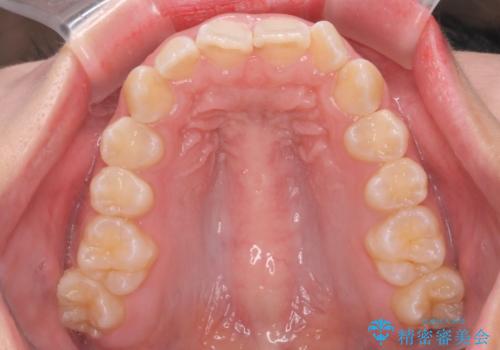

前歯の並び インビザライン 非抜歯で 深いかみ合わせの治療

- 前歯の並びを気にして来院。

上の前歯が内側に倒れこんでいました。

インビザラインで前歯の並びを整えています。

前歯の重なりが大きいいわゆる過蓋咬合を呈していましたが、ある程度適正な重なりにすることができました。